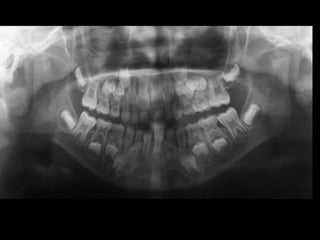

Panoramic (reconstructed from CT)

The most likely diagnosis for the facial asymmetry of this young girl is an

undiagnosed condylar fracture that most likely happen when she falled on a meta

crossbar bar ladder 2 or 3 years ago while she was 4 - 5 years old or so. The

condylar stump has healed and a new condylar head has formed, but the losted

substance of the condyle is gone. Therfore, the height of the ramus has

shortened.

The left ramus and condylar neck are shorter and the left eminence has no slope

if any. Healing and normal growth had reshaped both condyle and eminence.

!

Read more

When looking to the condyle from an anterior view, one can see the oblong

shape of a condyle but the left condyle is smaller.

The midline are not coincident. Note that the lower midline is toward right like

the occlusal plane canting to the right. This can be explained by the lack of

heigh of the left ramus and as normal growth occur, there is a wagon wheel

effect and the midline deviate toward the normal side, the occlusal plane is

moving up on the affected side.